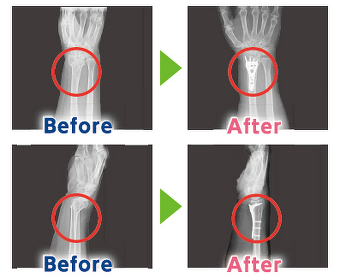

③早期治療で自分らしい生活を取り戻そう 高齢者の骨折治療

②早期治療で自分らしい生活を取り戻そう 高齢者の骨折治療

①早期治療で自分らしい生活を取り戻そう 高齢者の骨折治療